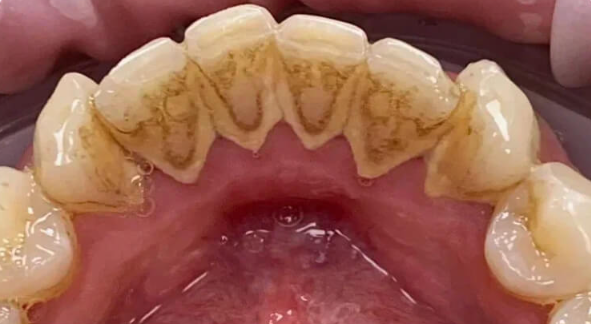

Профессиональная гигиена особенно важна при ортодонтическом лечении, ведь в повседневной жизни, дома, очень сложно поддерживать должный уровень гигиены полости рта! Даже если вы используете ирригатор и специальные ёршики! В нашей рубрике «до/после» вы видите то, что может быть с зубами при лечении брекетами, если не проводить своевременную чистку у врача-стоматолога. Марухно Дарья Александровна провела профессиональную чистку в несколько этапов, чтобы вернуть пациентке белизну ее собственных зубов! Брекет-система была поставлена не в нашей клинике, и почему пациентка не обратилась за профессиональной помощью раньше-вопрос) Но в данном случае, главное – итог! Кровоточивость после даже обычной чистки в такой клинической ситуации – естественный результат. Ведь обильный зубной налёт и зубной камень вызывают воспаление дёсен в виде гингивита, а порой даже пародонтита.

Доктор: Марухно Дарья Александровна